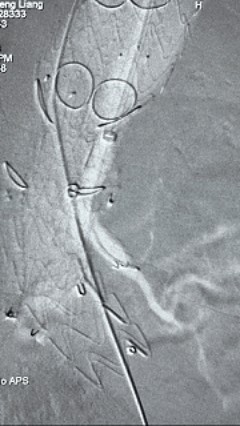

8. 从右侧股动脉入路送入腹主支架AB-24-12-110-S,近端重叠胸腹主动脉支架远端,调整好支架位置后释放。

9. 经左股动脉送入导丝导管,超选进腹主动脉支架短腿内,后沿导丝送入髂支,同理,右侧沿导丝送入髂支并释放,使用J9集团国际顺应性球囊后扩各支架连接处及支架近远端,最后通过预留导管向瘤腔注入人纤维蛋白粘合剂数支,造影显示分支通畅。

G-Branch在本例手术中展现出对扭曲解剖结构的出色适应性,针对该患者严重扭曲的瘤颈,支架系统的优异柔顺性使其能够顺利通过复杂路径,完成内脏分支血管的重建。